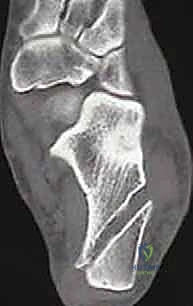

* الأشعة السينية (X-rays): لاستبعاد وجود كسور قديمة غير ملتئمة، أو وجود نتوءات عظمية، وتقييم محور القدم.

* التصوير بالرنين المغناطيسي (MRI): هو المعيار الذهبي. يوضح بدقة متناهية حالة الأربطة (تمزق جزئي، تمزق كلي، أو تندب)، ويساعد في الكشف عن أي إصابات مصاحبة مثل تمزق الأوتار الشظوية أو إصابات الغضروف المفصلي (Osteochondral Lesions).